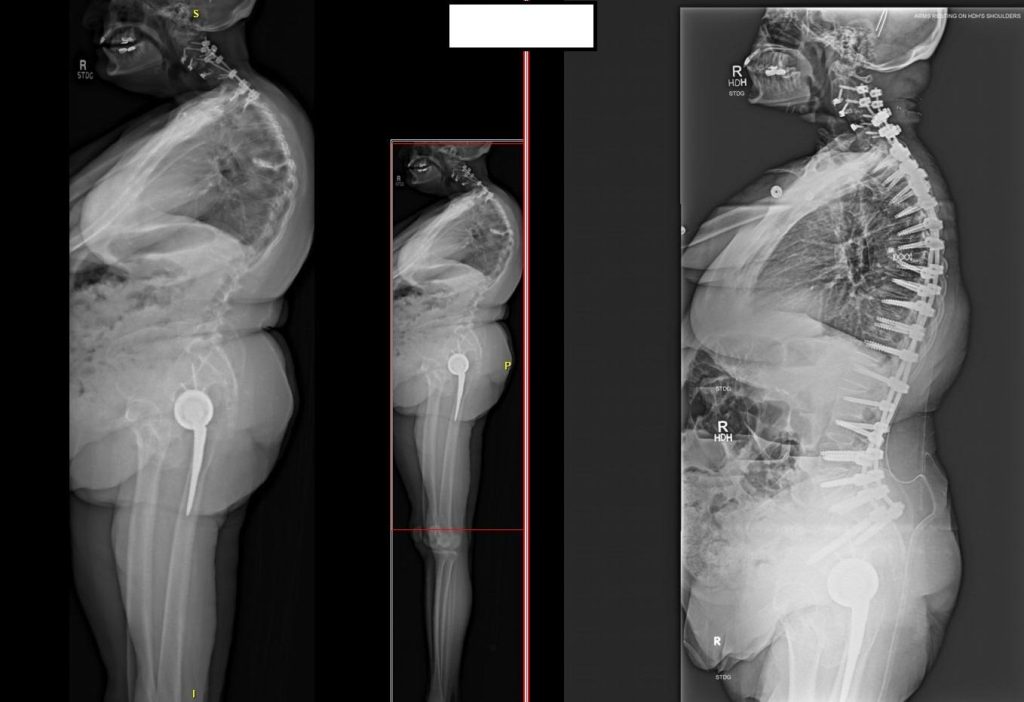

Dr. Elder says some adult deformity surgery as well as reconstructive and revision surgeries involve attaching screws or other hardware to strengthen and stabilize the spine.

“If you think about putting a screw into drywall or into a stud, there’s a big difference. And so some of the patients with severe bone density issues or severe osteoporosis, their bone is not even drywall, it’s kind of the paper on the drywall. So if we put screws into it, they’ll pull out immediately,” he says.